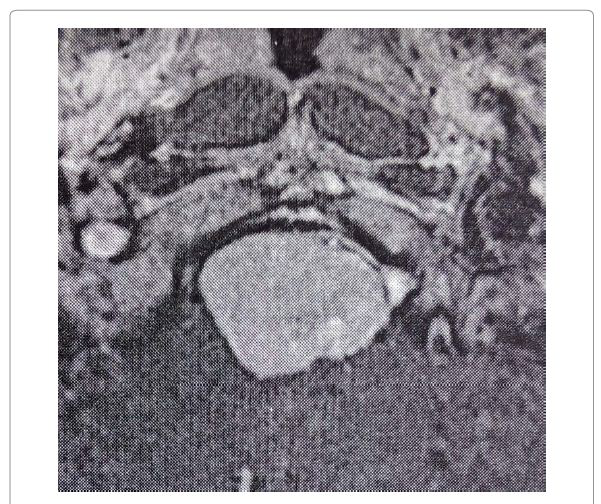

经过仔细详细的病史和体格检查,她还报告了较近(几周)发作的轻度吞咽障碍(吞咽困难)和左颊和舌头微微麻木。她接受了脑部和颈部磁共振成像(MRI)扫描,发现前部有肿块(T1上为等强度,T2上为高强度,弥散加权序列上为低点,具有均一的对比度增强,清晰的边界和特征性硬脑膜尾巴)大孔的边缘压缩长延髓并向后移位(图1和图2)。

病变的较大尺寸为21mm(前后),28mm(横向)和28mm(垂直)。枕骨大孔尺寸为35毫米(前后)乘28毫米(横向)。术前数字减影血管造影显示肿瘤是由左侧咽升动脉提供的。

图2 :术前轴向对比增强的T1WI MRI扫描